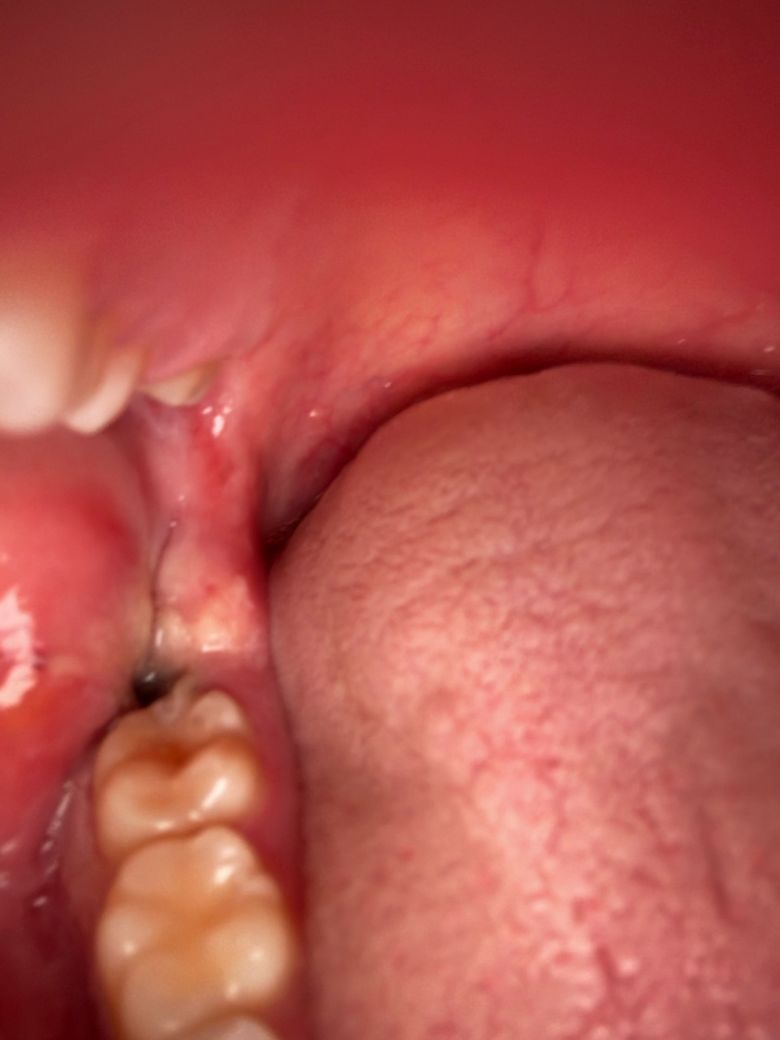

사랑니뽑은자리의피떡이 이상하게 변했어요

수요일날 발치를 했는데요 원래 피떡이 있던 자리에 지금보니 저렇게 크기도 훨씬작아지고 색깔이 거의 검정색에서 회색으로 보이게 변했어요 특히 크기가 엄청작아지고 주변에 하얀색으로 덮혔습니다 드라이소켓이 구취나고 회색으로 변한다던데 혹시 드라이소켓일 가능성이 있나요??ㅠㅠ

불행 속이 생긴다면 해당 부위에서 냄새가 나거나 통증이 매우 심하게 발생되게 됩니다. 냄새나 통증이 심하지 않는다면 드라이소켓이 아닐 가능성이 높습니다. 사랑니가 아무는 과정에서 해당 부위 혈병등의 형성될 수 있으며 사랑니가 발치된 부위는 자극을 하지 않은 것이 좋습니다.

사랑니 발치를 하고나서 잇몸이 아물면서 생기는 자연스러운 현상이니 너무 걱정하지 않으셔도 될것같습니다.

드라이소켓은 통증이 극심하기 때문에 아닐 것이며 사진상으로도 특별히 문제는 보이지 않습니다.

지금으로선 특별히 치유에 문제가 있어 보이진 않습니다 발치 후 주의사항 잘 지키시면 됩니다